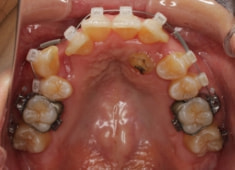

治療開始から24ヶ月後